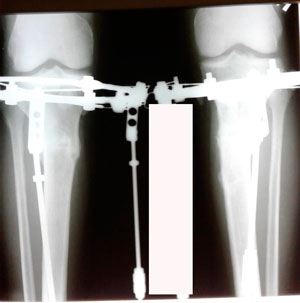

9 - ый день круток

image-13-03-20-02-18.jpg